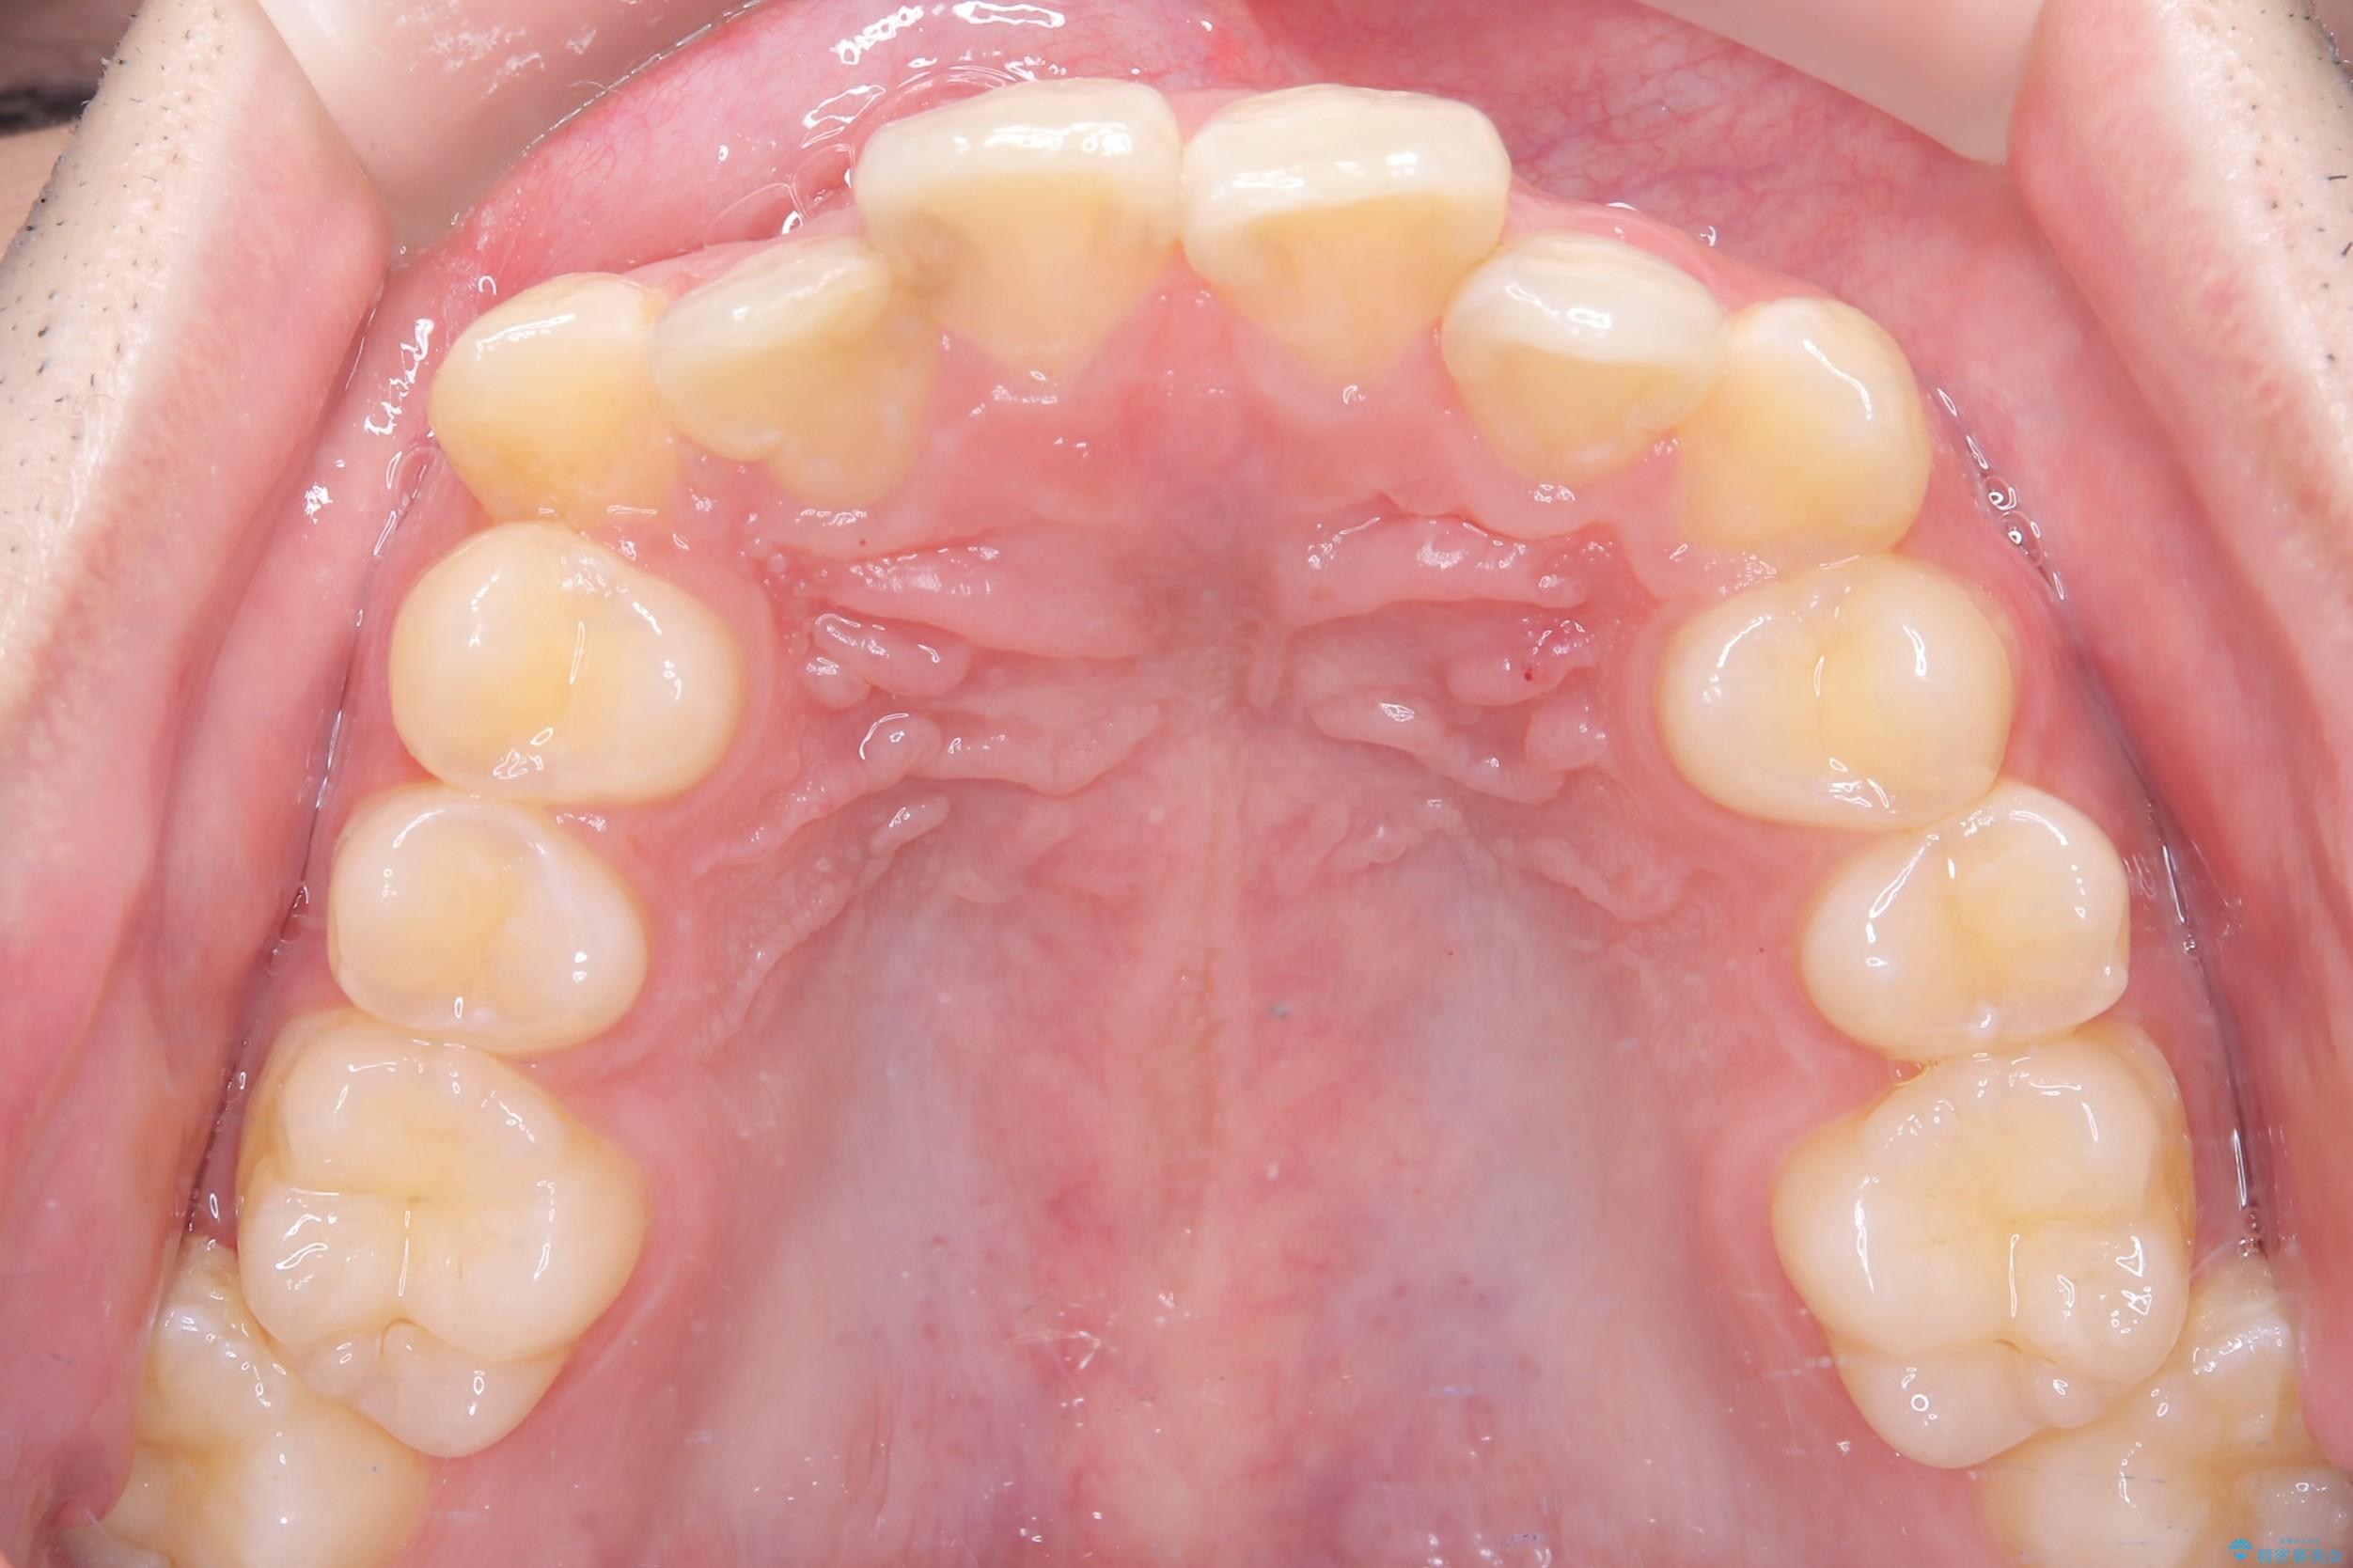

- 主訴:右上の前歯が何しなくても痛い

右上2番の歯に自発痛を認め、症状や歯髄診・レントゲン像から不可逆性歯髄炎と診断し、精密根管治療から歯冠補綴まで行うこととなりました。

初診時に歯髄診断を行い、不可逆性歯髄炎と診断し抜髄から補綴修復までの流れを説明し、精密根管治療、ファイバ-コア築造、オールセラミッククラウン(St)修復を行うこととしました。